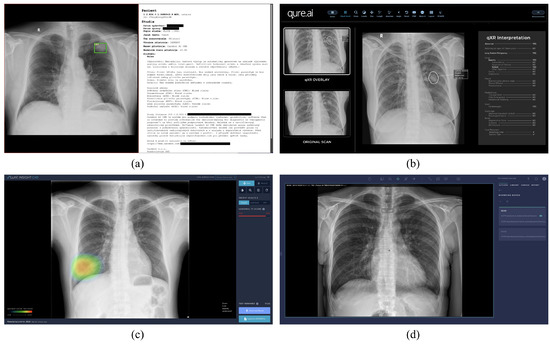

3.1. Software

3.1.1. Training Data

3.1.2. Model Architecture

3.1.3. Communication Protocol